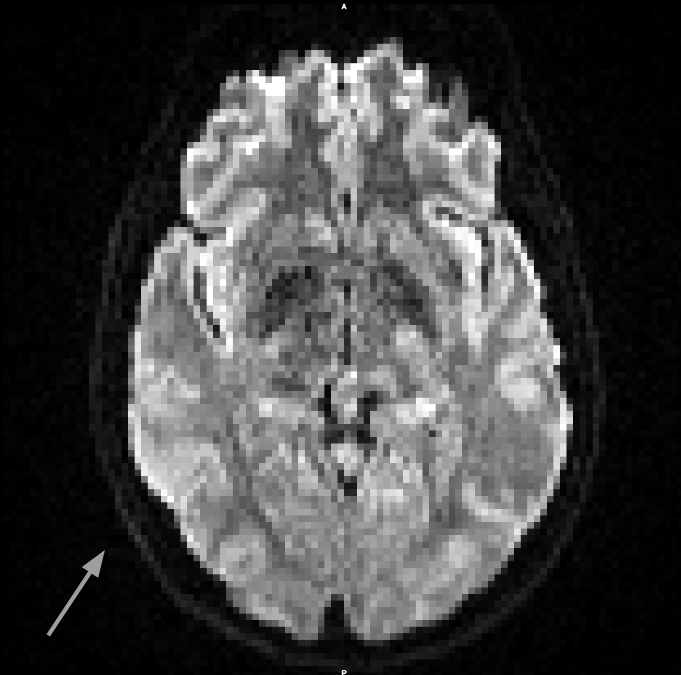

From these datasets, we use the five non-diffusion weighted () MRI scans each, as well as 30 diffusion weighted images (, diffusion gradient duration , spacing ). Each image consists of voxels with a resolution of . The data, and the effects of subject motion, are illustrated in Figure 6.

It can be seen in Figure 6 that subject motion during different phases of the acquisition leads to different types of artifacts. Results in Table 1 include the motion correction described in Section 3.3, which compensates spatial misalignments of different scans. However, motion can also lead to signal dropouts or to distortions within scans, which our current codec does not explicitly account for. This explains why q-space inpainting is less effective on the second as compared to the first scan. However, even on this challenging dataset that exhibits unusually strong artifacts, q-space inpainting still provides a benefit compared to all other alternatives.